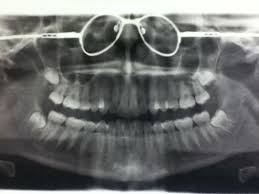

Don T Forget To Take Your Glasses Off Before Getting A Dental X Ray Cammarata Pediatric Dentistry Houston Tx Www Kids Teeth Com Dental Humor Denta